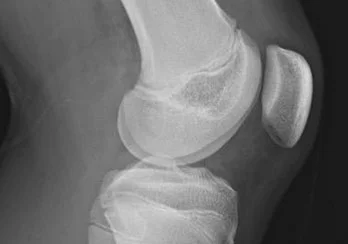

O próprio nome já diz, quando vista no perfil, a patela encontra-se um pouco mais alta que o normal fisiológico. Basicamente, a patela está um pouco acima de sua posição normal, na tróclea femoral.

A patela se articula na tróclea femoral, que funciona como um trilho para a patela movimentar-se. Toda vez que o joelho dobra e estica a patela corre sobre a tróclea. Quando ocorre a flexão, a patela desliza para baixo, toda a força é distribuída entre essas duas estruturas. Quanto mais homogêneo o movimento, melhor essa dissipação e menor a sobrecarga na cartilagem.

Nessa posição mais alta, quando entrar na tróclea ‘para correr no trilho’, acontece um contato menor entre a patela e a tróclea. Baseado nas leis da física, quanto menor a área de contato, maior a pressão. Portando, podem acontecer dois problemas:

A radiografia é o exame mais acessível e fácil de ser realizado. Existe diversos índices para fazer essa mensuração da altura patelar. Por recomendação da literatura, usamos bastante o índice de Insall-Salvatti, que consiste em medir o maior comprimento da patela e divide esse valor pelo comprimento do tendão patelar. O normal na população é 1, quanto menor o índice, mais alta será a patela.